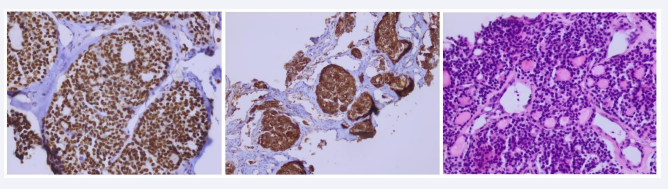

The patient’s thyroid workup was normal, with TSH at 2.1 mIU, T3L at 2.1 umol/L, T4L at 14 pmol/L. In the absence of flexible bronchoscopy, which was difficult to perform because of the cervical masses and refused by the patient, a transparietal biopsy of the right apico-dorsal process revealed on histological study a secondary localization of a follicular thyroid tumor (Figure 5).

Figure 5: Histological study of transparietal biopsy, showing fibrous tissue infiltrated by an endocrine tumor proliferation, partially follicular.